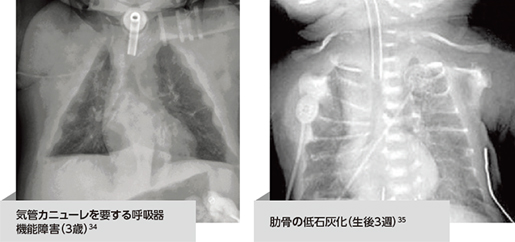

- 低ホスファターゼ症(HPP)患者さんにおける呼吸器障害は、進行性の呼吸機能障害から呼吸不全に至るまでさまざまですが、これらは胸腔容積の減少および肺の低形成に起因します2-5

- 挿管、人工呼吸器、あるいは酸素補給を要する呼吸機能障害2-4

- 人工呼吸器を使用しても肺炎や呼吸不全を起こす2-4